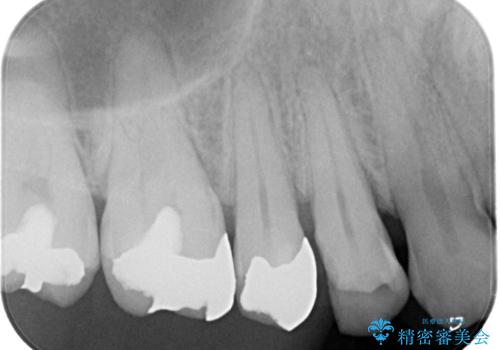

- 銀歯が取れたことを主訴に来院されました。

虫歯も認め、虫歯を除去したのちセラミックインレーにて修復しております。

適合のよい修復を行うことで、再び虫歯になることを予防します。